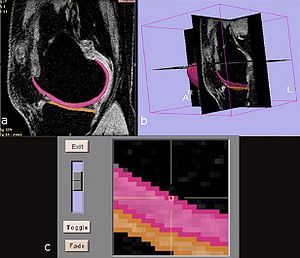

- 3.15 A Multidimensional Dynamic Quantification Tool for the Mitral Valve

Treatment Planning and Delivery of Whole Brain Irradiation with Hippocampal Avoidance in Rats

|

Publication: PLoS One. 2015 Dec 4;10(12):e0143208. PMID: 26636762 | PDF Authors: Cramer CK, Yoon SW, Reinsvold M, Joo KM, Norris H, Hood RC, Adamson JD, Klein RC, Kirsch DG, Oldham M. Institution: Department of Radiation Oncology, Duke University Medical Center, Durham, NC, USA. Background/Purpose: Despite the clinical benefit of whole brain radiotherapy (WBRT), patients and physicians are concerned by the long-term impact on cognitive functioning. Many studies investigating the molecular and cellular impact of WBRT have used rodent models. However, there has not been a rodent protocol comparable to the recently reported Radiation Therapy Oncology Group (RTOG) protocol for WBRT with hippocampal avoidance (HA) which is intended to spare cognitive function. The aim of this study was to develop a hippocampal-sparing WBRT protocol in Wistar rats. Methods: The technical and clinical challenges encountered in hippocampal sparing during rat WBRT are substantial. Three key challenges were identified: hippocampal localization, treatment planning, and treatment localization. Hippocampal localization was achieved with sophisticated imaging techniques requiring deformable registration of a rat MRI atlas with a high resolution MRI followed by fusion via rigid registration to a CBCT. Treatment planning employed a Monte Carlo dose calculation in SmART-Plan and creation of 0.5 cm thick lead blocks custom-shaped to match DRR projections. Treatment localization necessitated the on-board image-guidance capability of the XRAD C225Cx micro-CT/micro-irradiator (Precision X-Ray). Treatment was accomplished with opposed lateral fields with 225 KVp X-rays at a current of 13mA filtered through 0.3 mm of copper using a 40x40 mm square collimator and the lead blocks. A single fraction of 4Gy was delivered (2Gy per lateral field) with a 41 second beam on time per field at a dose rate of 304.5 cGy/min. Dosimetric verification of hippocampal sparing was performed using radiochromic film. In vivo verification of HA was performed after delivery of a single 4Gy fraction either with or without HA using γ-H2Ax staining of tissue sections from the brain to quantify the amount of DNA damage in rats treated with HA, WBRT, or sham-irradiated (negative controls). Results: The mean dose delivered to radiochromic film beneath the hippocampal block was 0.52Gy compared to 3.93Gy without the block, indicating an 87% reduction in the dose delivered to the hippocampus. This difference was consistent with doses predicted by Monte Carlo dose calculation. The Dose Volume Histogram (DVH) generated via Monte Carlo simulation showed an underdose of the target volume (brain minus hippocampus) with 50% of the target volume receiving 100% of the prescription isodose as a result of the lateral blocking techniques sparing some midline thalamic and subcortical tissue. Staining of brain sections with anti-phospho-Histone H2A.X (reflecting double-strand DNA breaks) demonstrated that this treatment protocol limited radiation dose to the hippocampus in vivo. The mean signal intensity from γ-H2Ax staining in the cortex was not significantly different from the signal intensity in the cortex of rats treated with WBRT (5.40 v. 5.75, P = 0.32). In contrast, the signal intensity in the hippocampus of rats treated with HA was significantly lower than rats treated with WBRT (4.55 v. 6.93, P = 0.012). Conclusion: Despite the challenges of planning conformal treatments for small volumes in rodents, our dosimetric and in vivo data show that WBRT with HA is feasible in rats. This study provides a useful platform for further application and refinement of the technique. Funding:

|

MRI with labeled structures from atlas registered to the CBCT. Registration was carried out with the open source imaging tool 3D Slicer, Version 4.4.0. |